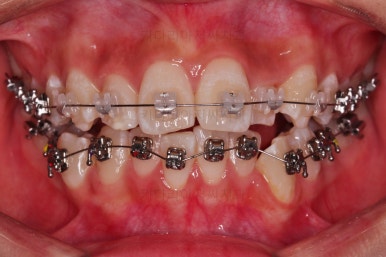

동래교정치과 초진 시의 입 안 모습이에요.

치열이 삐뚤고 덧니가 보이네요.

이번 환자분도 스스로는 보기 싫은 이유가 첫 번째였지만 사진에서도 보시다시피 양치가 잘 안되어 치석도 많고 잇몸도 부어있는 상태였어요.

그리고 앞니들이 마모가 많이 되어 있어서 각각의 치아들이 원래 형태에서 많이 변형된 것을 볼 수 있네요.

동래교정치과 장치를 부착한 직후의 모습입니다.

입은 약간 더 튀어나오는 편이었고 상대적으로 많이 보이는 윗니를 세라믹으로 해서 아랫니는 메탈이라 하더라도 심미적으로 크게 손해는 아니었어요.